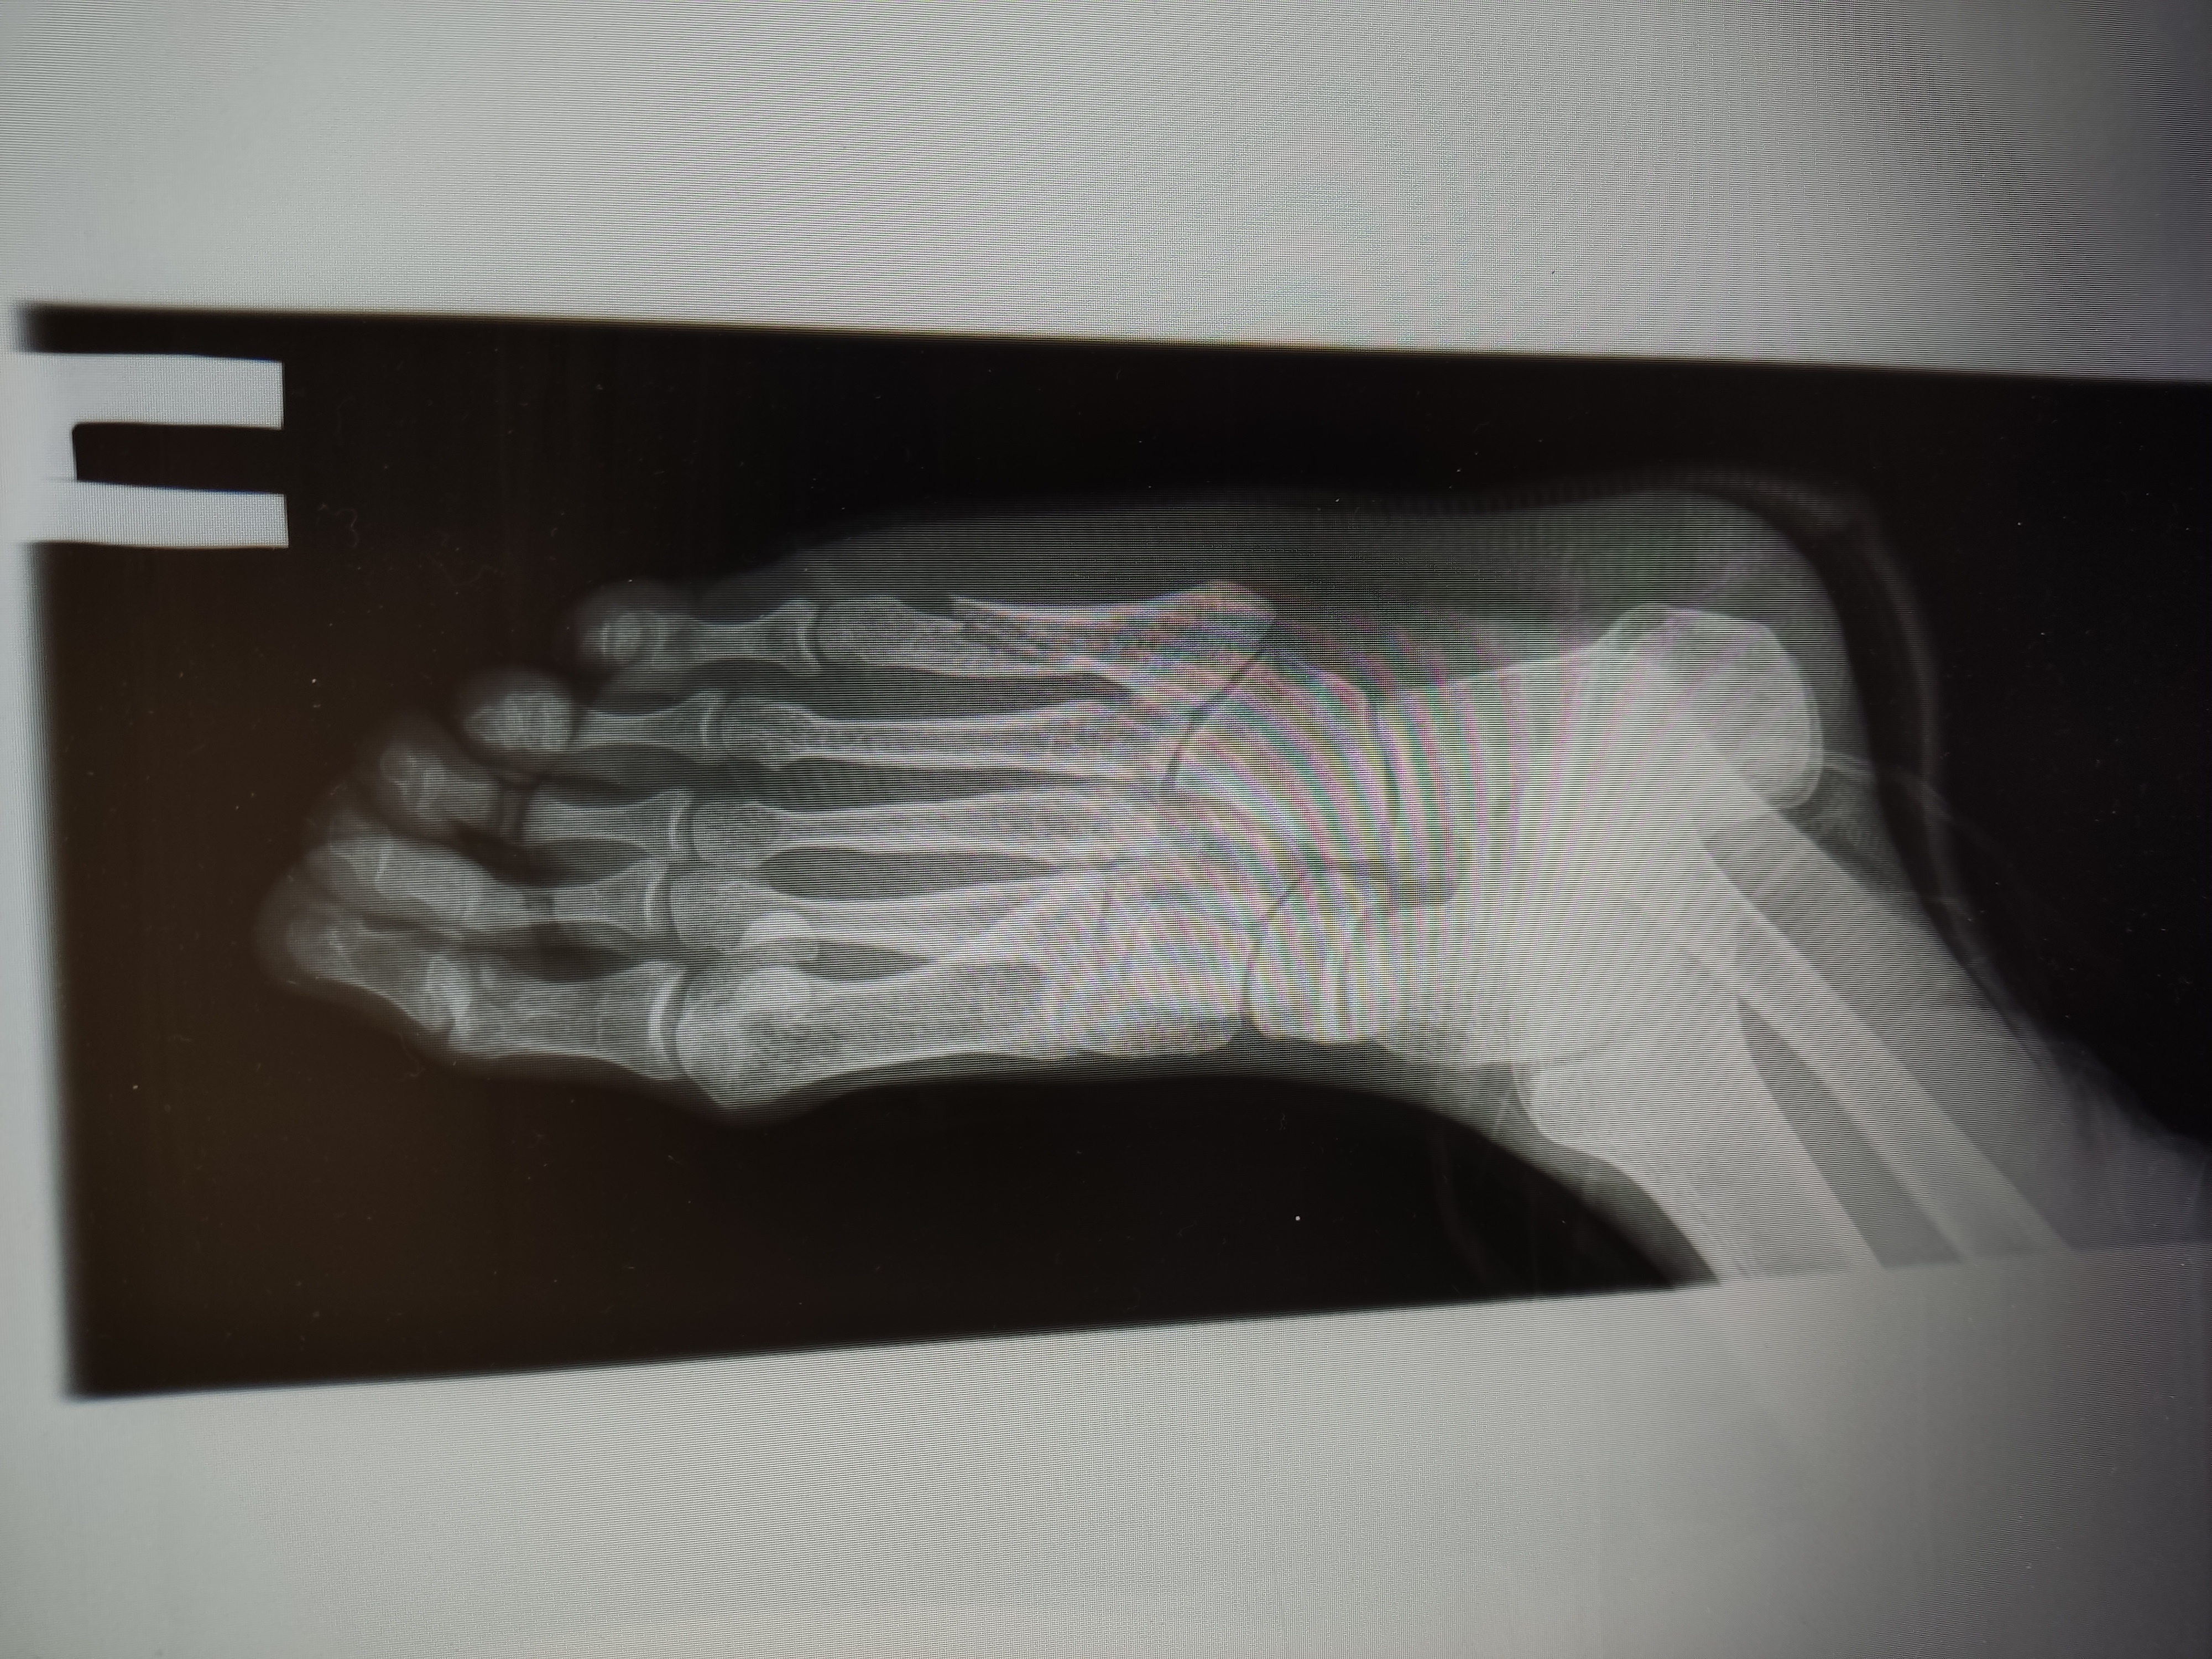

1280x540

Ну шо парни это к вам? Теперь даже на заводе не смогу работать?

>>1629165

Мелочи вообще. Пока суставная щель в норме. Остеопороз не нашли. Бегай пока. Аккуратно.

Аноним 03/07/25 Чтв 18:36:37 1629760 78

>>1629584

Да это понятно, как следить за этой хуетой? Я вот хочу отучиться на оператора станков ЧПУ и пойти работать. Стоит ли идти? Или через 2-3 года у меня сустав перейдёт в третью стадию? Ещё работать стоя нельзя или тяжёлая физ работа? Крч говоря можно пожалуйста больше информации. Меня почему то к ревомтологу отправили а не к артопеду.